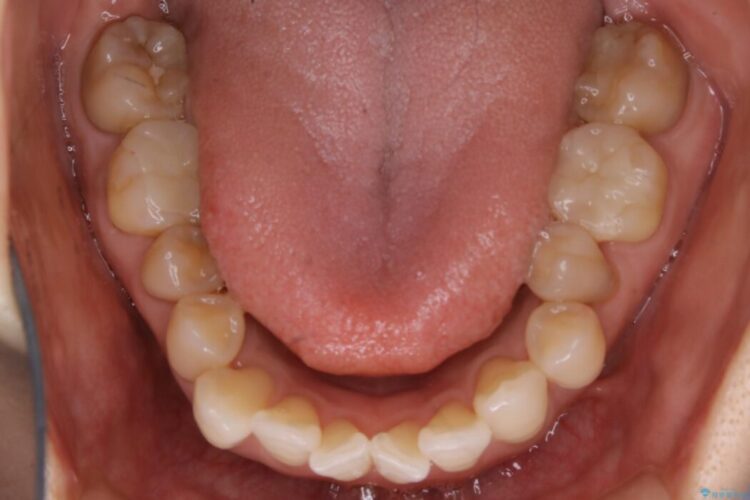

【30代女性】前歯の反対咬合をマウスピースで改善

前歯のガタつき、噛み合わせの不調を改善したいとご来院されました。

全体的に歯列が狭窄しており、本来外側に覆いかぶさっている上の前歯が内側に入り込んでいました。

歯列弓全体の形状を整えるとともに歯の大きさもコントロールすることで非抜歯にて矯正を行いました。

気になっていたガタつきも改善され、患者様にはご満足いただけました。